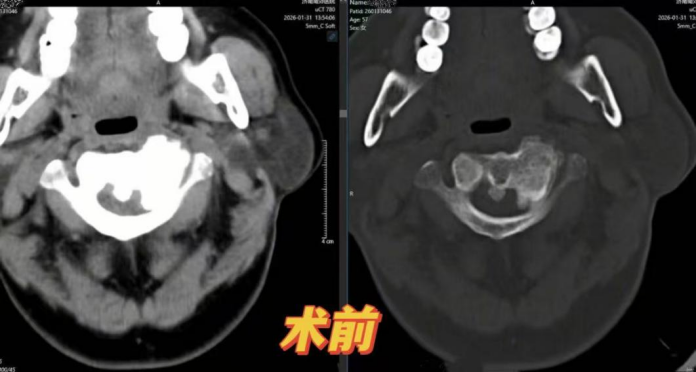

“左侧颈肩疼了半年,左手还一直发麻……”近日,饱受折磨的57岁患者李女士(化名)来到济南南郊医院脊柱外科,副主任孙泉接诊后,通过完善颈椎CT、MRI及血管造影等术前检查,最终锁定“元凶”——寰枢椎长期半脱位引发骨质增生,压迫神经。

寰枢椎,这个连接颅脑与脊髓的“生命中枢”,因解剖结构复杂、紧邻椎动脉和延髓,被业内视为“手术禁区”。稍有不慎便可能引发瘫痪、大出血等致命风险,全国能独立开展此类手术的团队屈指可数。面对挑战,孙泉副主任带领团队迎难而上:完善的术前辅助检查 包括颈动脉血管的造影 甚至一些寰枢椎的重建,到颈动脉造影规避血管损伤风险,术前筹划细致到毫厘。